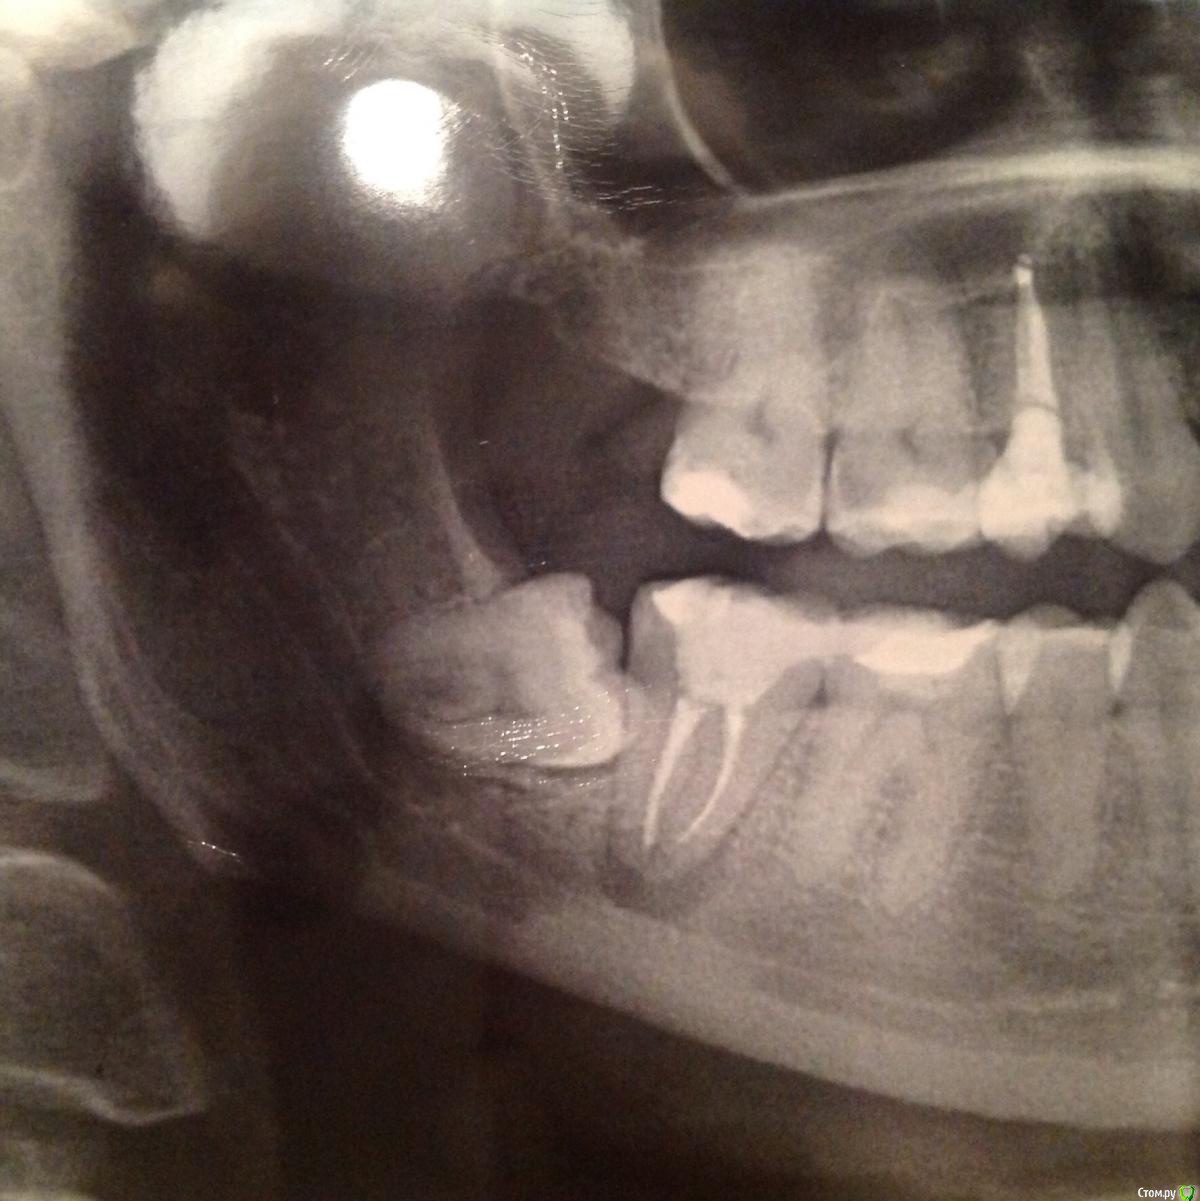

Катруся Опубликовано 30 марта, 2015 Поделиться Опубликовано 30 марта, 2015 (изменено) Добрый!Подскажите, пож-та. У меня болит нижняя семерка правая, депульпированная. Боль ноющая, при надавливании усиливается, на холод/горячее не реагирует. Каналы запломбированы несколько лет назад. Жаловалась в течение этих лет неоднократно своему врачу, но из за зуба мудрости, который лез в семерку, мы думали что болит из за него, т к после депульпирования делали снимок и каналы проверяли на качество заполнения. Зуб мудрости, который на снимке в наст момент удален (4,5 месяца). Снимку тоже 4,5 месяца. Судя по снимку у меня киста... Это я уже сейчас вижу, после того как провела собственное так сказать расследование... Врачи этот снимок видели: и хирург и мой врач-стоматолог... Ничего не сказали.... Подозревать их в некомпетентности у меня нет оснований, т к лечу у них все очень долго и вся моя семья тоже ... Но все же, бывает всякое....Подскажите, каналы запломбированы нормально? Или киста, если это киста, образовалась из за того, что они не до конца заполнены... Или она образовалась из за неверно росшей восьмерки???? Спасибо Изменено 30 марта, 2015 пользователем Катруся Ссылка на комментарий

Гарриевич Опубликовано 30 марта, 2015 Поделиться Опубликовано 30 марта, 2015 Если его лечила n лет назад, а сейчас там такая картина, то нужно перелчиватьНо для точного ответа нужен снимок до лечения (до депульпирования)И второй момент, "киста" на 7ке не имеет прямой связи с зубом мудростиЛечение проводилось с использованием коффердама? Ссылка на комментарий

Катруся Опубликовано 31 марта, 2015 Автор Поделиться Опубликовано 31 марта, 2015 Сходила сегодня к врачу. Сделали там снимок, пришел еще один врач и хирург, долго смотрели все на экране... Короче, все сошлись что каналы запломбированы хорошо, зуб выглядит отлично. Общупали мне всю нижнюю челюсть, ничего у меня там не болит, только зуб ноет и при жевании. В итоге врач мне его подспилила и вывела из прикуса, боль ушла сразу. Назначила лечение ( антибиотик, нпвп и антигистаминные) и сказала понаблюдать, если боль вернется - бежать к ней, будем делать 3d снимок и перелечивать.... А какова вероятность что периодонтит такого размера как у меня может пройти без физического вмешательства? Ссылка на комментарий

Катруся Опубликовано 3 апреля, 2015 Автор Поделиться Опубликовано 3 апреля, 2015 Добрый. Пишу отчет о походе к другому врачу, может кому то интересно. Мне сделали МРТ, посмотрели все в 3d, корни (3 шт) пролечены хорошо на всем протяжении... Однако верх одного оказался загнутым, вероятно в этом проблема.... Хотя и эта врач точно сказать не может, почему такое воспаление.... Размер пораженной области 0,8 на 0,3 см. Лечить будем в 4 этапа. На первом надеемся открыть все корни за раз, все там промыт, вложить лекарство и закрыть временной пломбой на 1 мес не меньше.... Ну и там по мере лечения будем смотреть динамику... Резекция не показана, т к на снимке корни в непосредственной близости от вены ( или артерии? Что там?), которая в нижней челюсти проходит... Вот такие дела. Как схожу на первый прием - напишу как все прошло. Спасибо откликнувшимся врачам! По стоимости: пока мне примерно посчитали 36 000. Ну и плюс я уже заплатила 3500 за МРТ. Вот так вот((( учитывая что я в отпуске по уходу ребенком, эта сумма сейчас оооочень существенна для меня... Берегите зубы, ищите хороших врачей... Ссылка на комментарий